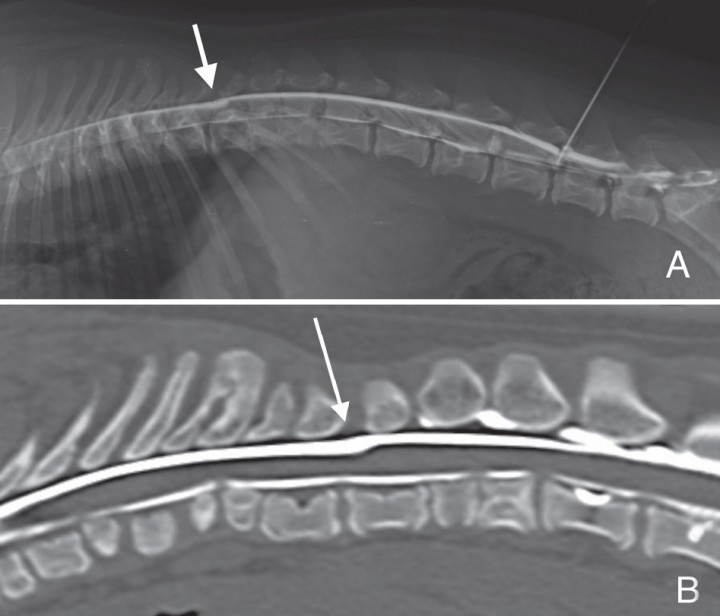

En la totalidad de los casos, los hallazgos radiológicos mostraron una dilatación dorsal o dorsolateral de la columna de contraste subaracnoidea, con desplazamiento y compresión del parénquima medular (Fig. 1). Los casos 1, 3, 5, 6, 8, 10 y 11, presentaron la forma típica de gota. En los restantes se observó una dilatación longitudinal del espacio subaracnoideo focal sin finalización abrupta, o en forma circunferencial. En el mielo-TAC, la extensión de la dilatación era variable, comprendiendo entre uno y cuatro cuerpos vertebrales y con un grado de compresión relativo de un 61’53% a un 99’82% (Fig. 2). En la Tabla 2 se muestra el grado de compresión medular relativo de la cavitación y su relación con la severidad de los signos clínicos.

<p>A. Mielografía proyección lateral derecha del caso 3 en el que se aprecia una dilatación del espacio subaracnoideo dorsal, con acúmulo de contraste iodado y reducción del grosor de la médula espinal a nivel del cuerpo vertebral T12. B. Reconstrucción sagital con algoritmo hueso correspondiente a mielo-TAC del mismo caso. Se observan numerosas hemivértebras y vértebras en mariposa en los segmentos vertebrales adyacentes a la cavitación.</p>

Figura 1

A. Mielografía proyección lateral derecha del caso 3 en el que se aprecia una dilatación del espacio subaracnoideo dorsal, con acúmulo de contraste iodado y reducción del grosor de la médula espinal a nivel del cuerpo vertebral T12. B. Reconstrucción sagital con algoritmo hueso correspondiente a mielo-TAC del mismo caso. Se observan numerosas hemivértebras y vértebras en mariposa en los segmentos vertebrales adyacentes a la cavitación.